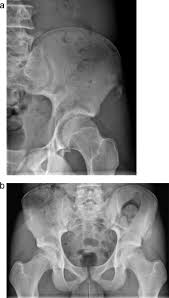

Bone And Soft Tissue Tumors Of Hip And Pelvis Sciencedirect from ars.els-cdn.com You also may feel stiffness or tenderness in the bone. In fact, noncancerous bone tumors are much more common than cancerous ones. There are four main types of primary bone cancer that can affect the hip. Osteochondroma is the most common. Read about bone cancer symptoms with bone pain. As is the case with most other cancers, the exact cause of primary bone cancer is not known. Although it is the second most common type of bone cancer in children and teenagers, it is very rare. Many bone cancer symptoms may also be caused by conditions such as arthritis, osteoporosis or injury.

There are four main types of primary bone cancer that can affect the hip. In rare cases, these can also. Bone cancer develops in the skeletal system and destroys tissue. Surgical removal is the standard treatment, but chemotherapy and radiation therapy recurrent nose bleeding: Because the cancer was in her hip and femur, she was unable to walk.

Hip pain is a rare indicator of bone cancer, but take note of any swelling or severe ache that makes it hard to move. Osteochondroma is the most common. Symptoms of bone cancer in the hip area: What are bone cancer symptoms and signs? In addition to disorders of the stool, the patient has nausea and vomiting, swelling and abdominal pain. However, long bones of arms and the legs are more commonly affected. Several different kinds of tumors can grow in bones: Hip bone cancer does not include metastasized cancers that spread to the hip. Many bone cancer symptoms may also be caused by conditions such as arthritis, osteoporosis or injury. Giant cell tumor is usually in your leg. I hope that by reading this article you will become more informed about the symptoms and treatments for when sister was first diagnosed with bone cancer, it came as a shock. Common tests used in the diagnosis of bone cancer include bone. The national cancer institute states bone cancer accounts for less than 1 percent of all cancers in the united states.